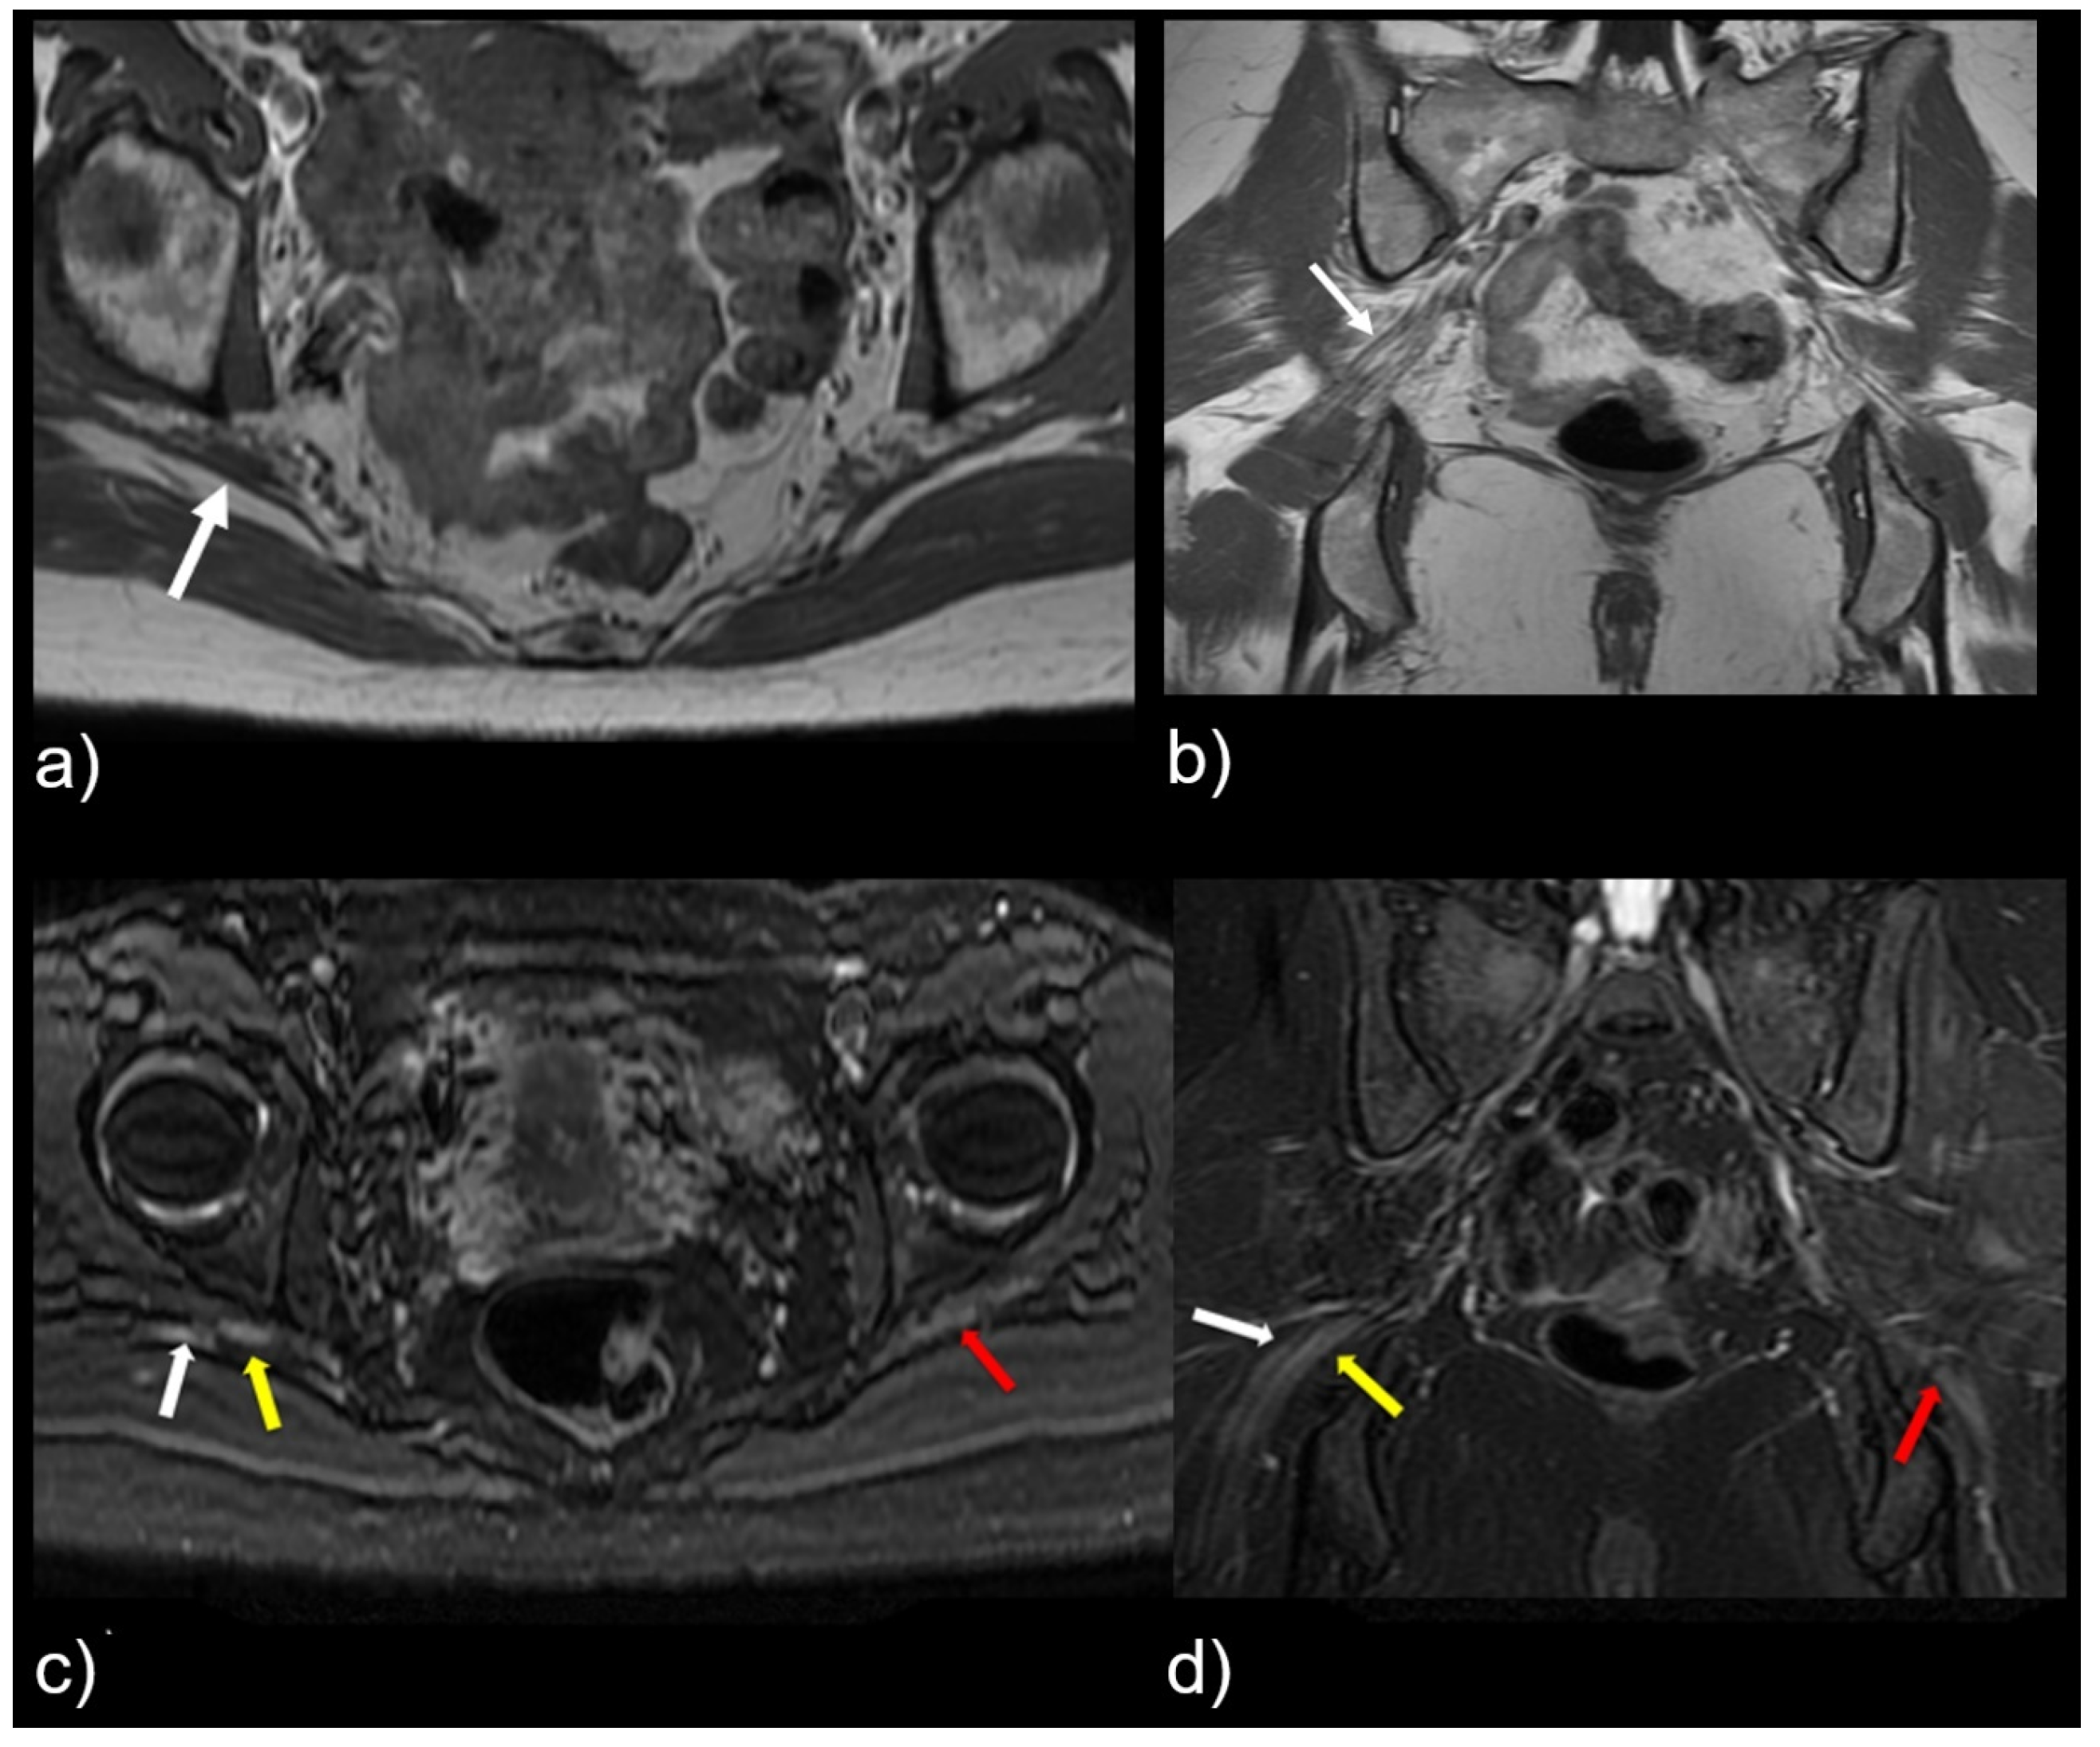

Figure 3.

Coronal T1-weighted sequence of the bilateral sciatic nerves showing a type II variant with a common peroneal nerve component piercing a bifid piriformis (white arrow), tibial nerve component running in normal position anterior and inferior to piriformis (black arrow).